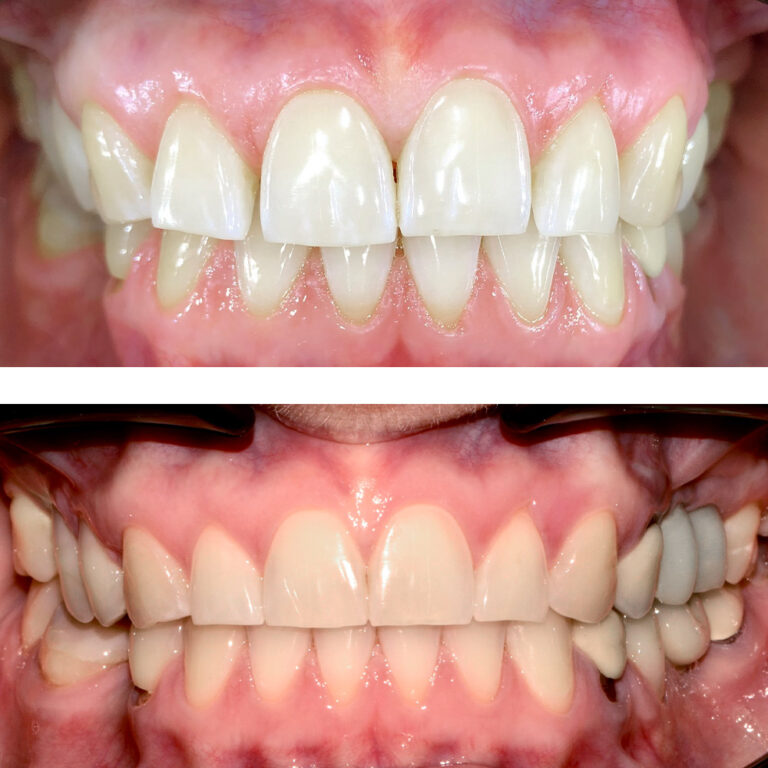

Кейс 23

Иванова Екатерина Сергеевна

Количество кап ВЧ 24

Количество кап НЧ 24

ДО

ПОСЛЕ